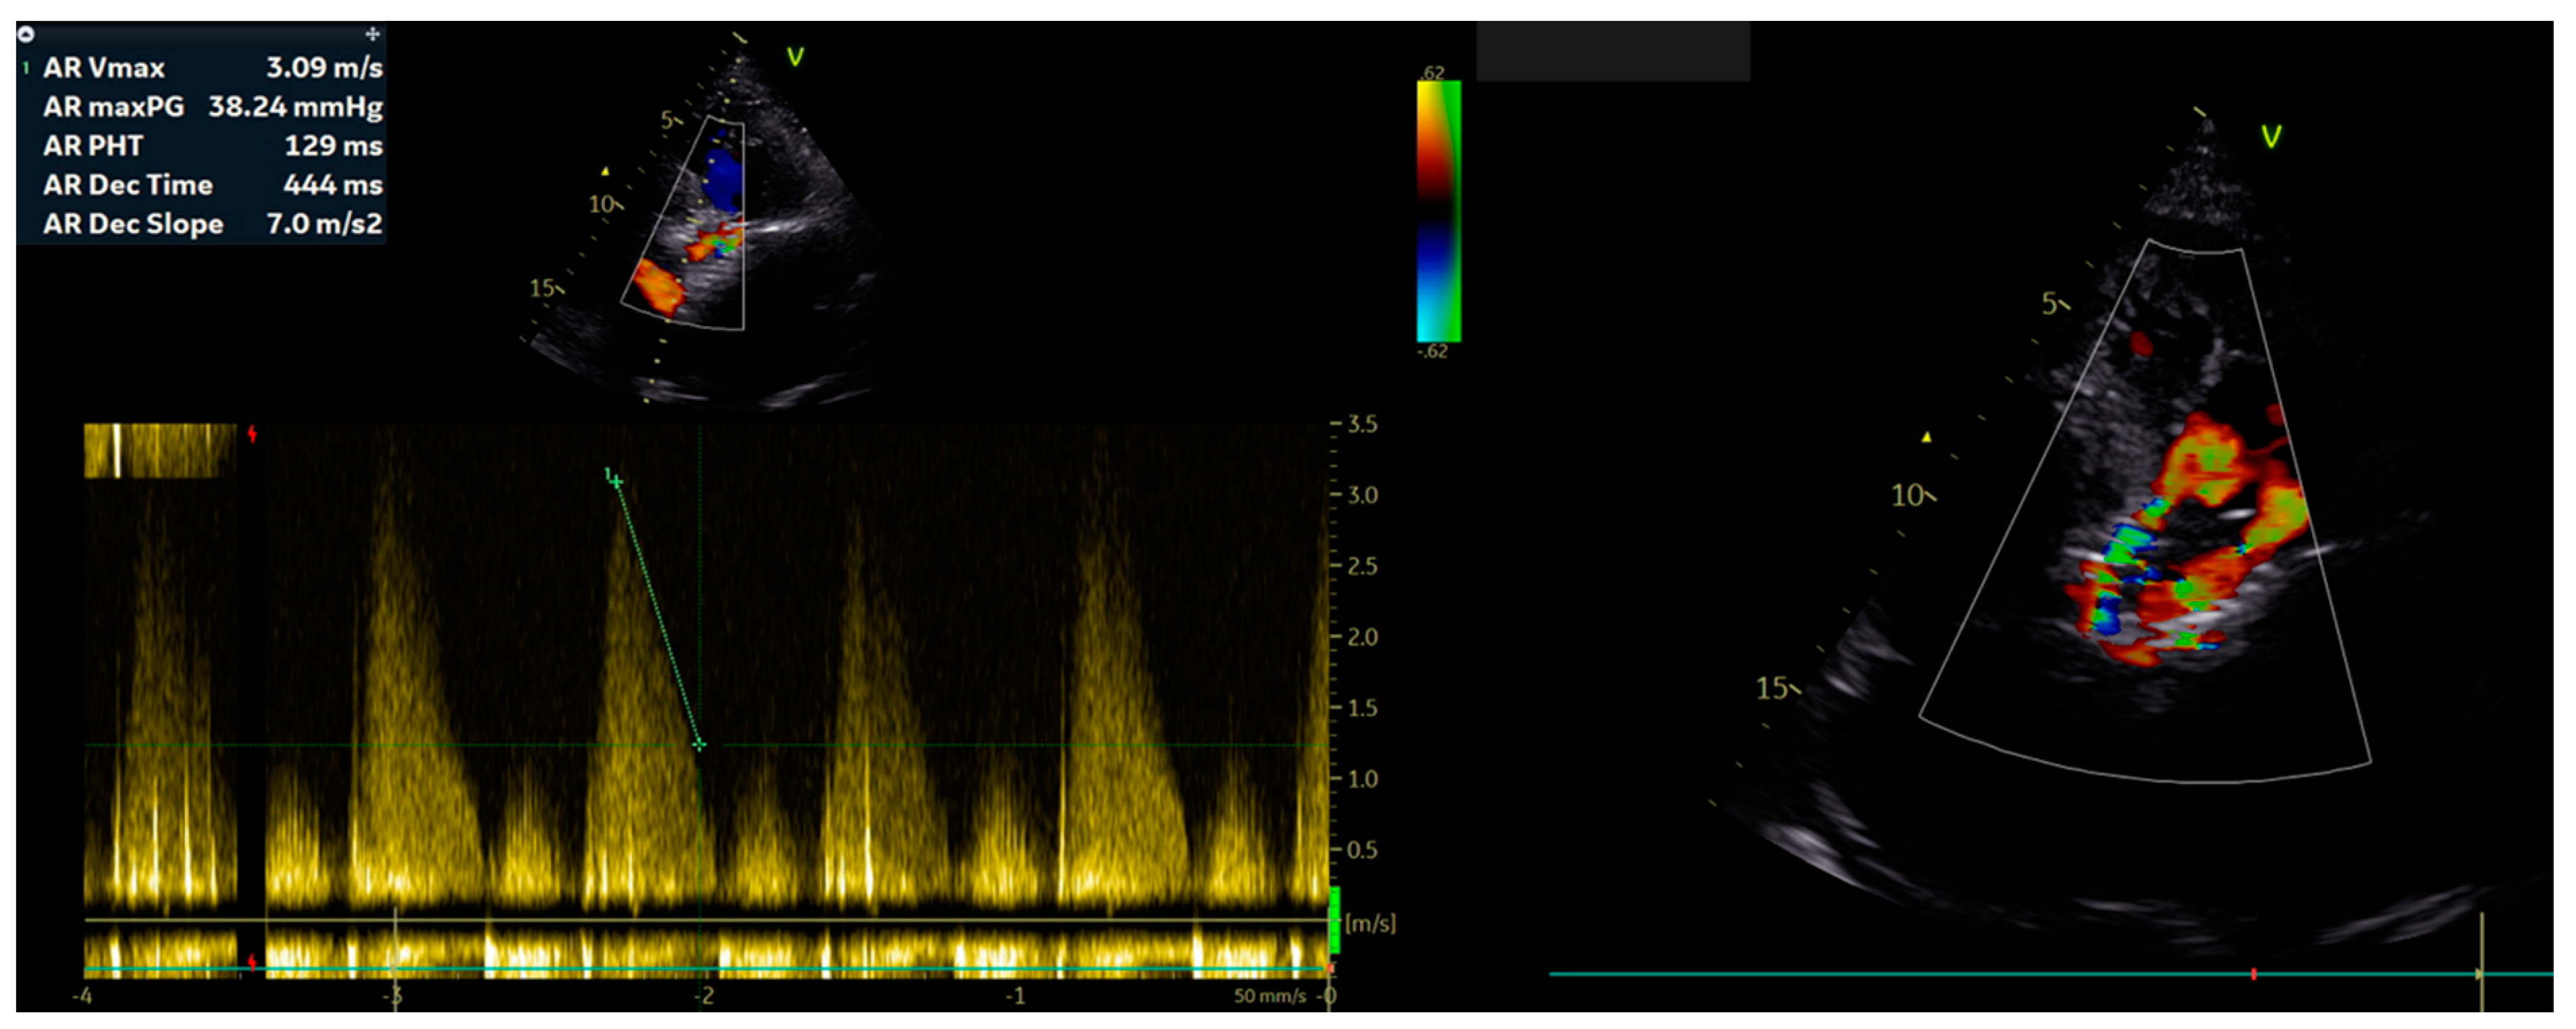

2. Case Report